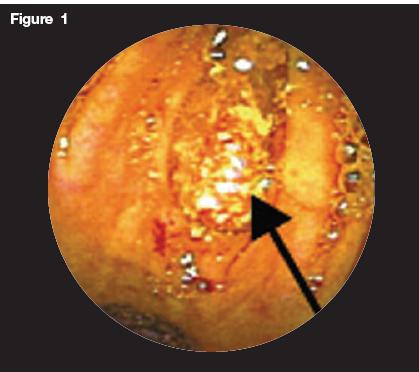

Laboratory analysis demonstrated a white blood cell count of 13 106/L(76% neutrophils). Findings from urinalysis were normal. Findings on a CT scan of the abdomen with contrast were normal with no evidence of appendicitis. Because of persistent abdominal pain with normal findings on the CT scan of the abdomen, colonoscopy was performed. Figures 1, 2, and 3 are images taken at the level of the terminal ileum. Figure 1 shows an impacted pill in the appendiceal orifice. Figure 2 shows the removal of the pill using forceps. Figure 3 shows mild residual inflammation of the appendiceal orifice after removal of the impacted pill.

Figure 1